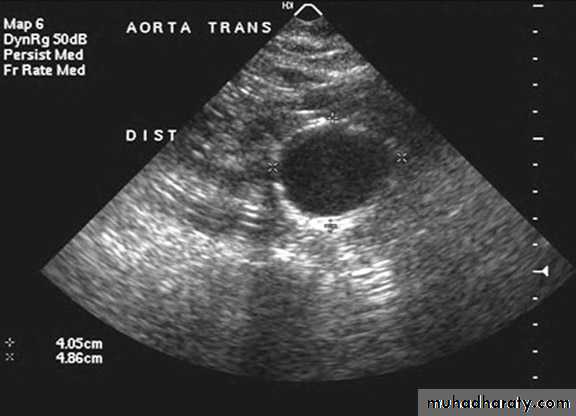

Ultrasonogram

• (AAAs) is true aneurysms commonly involve the infrarenal aorta. aortic diameter >3 cm = AAA.• An AAA of any size can rupture, but those >5 cm are more likely to rupture.